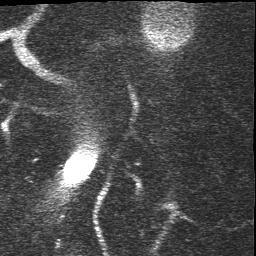

Refer to caption

(a) Original Image

(b) SNIC, DICE 81.6%

(c) EA, DICE 81.3%

(d) Ours, DICE 87.9%

(e) Ground Truth

Figure 7: Qualitative Comparison of Superpixel Algorithms on an image from DeepVess.

The results in Table 1 show that our approach performs best across other superpixel algorithms in an end-to-end segmentation pipeline. Based on this observation we conclude that the slight drop in compactness we observed in the natural image experiments with respect to EA does not affect the quality of post-processing. Moreover, the results stress our method’s robustness with respect to noise. It is also worth noting that it closely matches the performance of a trained neural networkand the second human annotation on this dataset. While the Double-DIP seems to work on natural images with a saliency estimate, it does not converge on noisy microscopic data which is why we decided to stop the optimization after 500 steps. In Figure 7 we can see superpixel based foreground predictions generated from a DeepVess slice. While SNIC fails to match superpixels to vessel structures and overfits to noise artifacts, EA and our method produce smoother superpixels. However, the Deep Decoder is better at detecting low-intensity shapes and adhering to vessel boundaries, as it can be seen around the ground truth objects in the top left part in Figure 7, which is why the segmentation pipeline works best with our method as a superpixel generator.